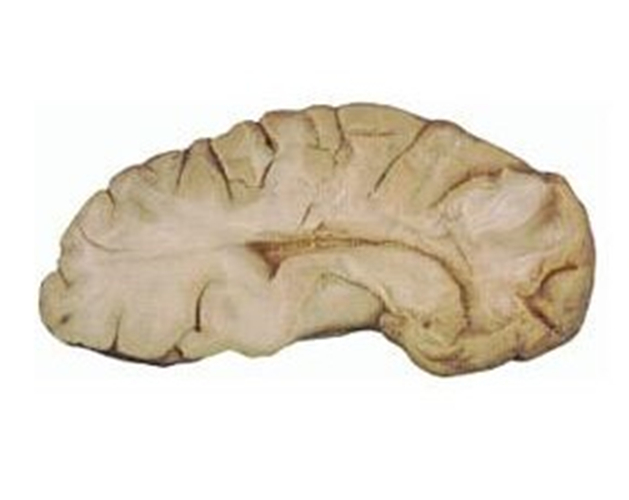

橄欖橋腦小腦腦萎縮標本

小腦腦萎縮解剖

腦萎縮醫學標本